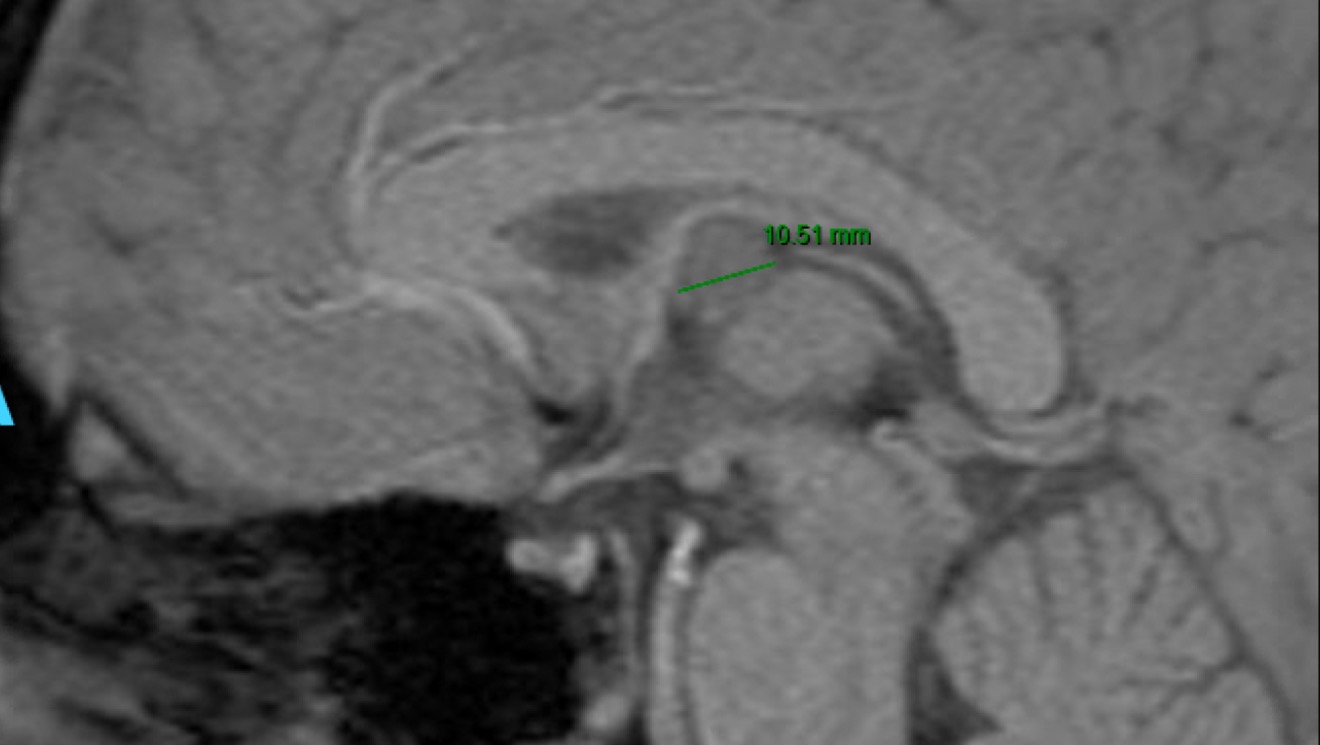

Harrison is 11 and has an extremely rare colloid cyst brain tumor. Every day he goes without brain surgery is a risk. The tumor acts as a ball joint and can cut off the spinal fluid to the brain, causing many complications, including instant death. Harrison’s tumor is small enough that it is not causing complications currently, but to avoid future complications, we have surgery scheduled for May 16th.